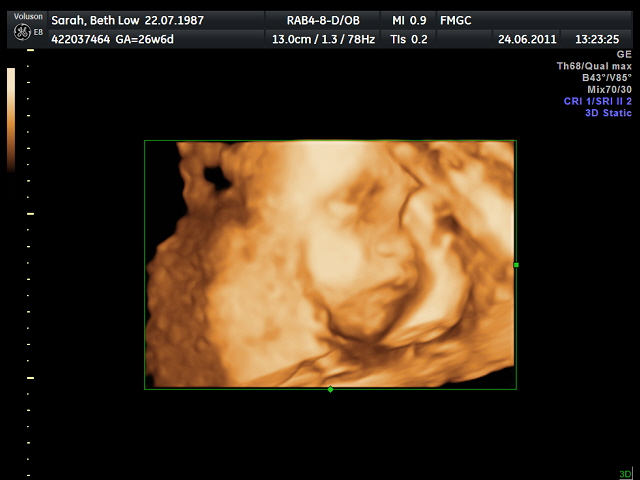

The 3D/4D Scan (Part 2)

Here she is!

The scan went as well as can be. Our first try was not so successful. She was turned inward toward my pelvis and had her hands covering her face. So the doctor checked all the vital organs, like liver, heart, lungs while waiting for her to reposition herself. He also checked her spine. Everything was in perfect order (not that I had expected anything less). It is just common procedure to check all the important things.

The doctor asked that I come back 30 minutes later for another try. He suggested I walk around and have something sweet to drink. This would help to reposition her. We sat at Starbucks for those 30 minutes talking to her. I was rubbing my belly and asking her to cooperate with the doctor. I must have looked silly but I didn't care. Elijah also talked to her and asked that she show us her pretty face! So 30 minutes later we went back. And sure enough, she had repositioned and we got a better look at her face! Half of her face this time, but it is better than no face. Her hands were still near her face but not in the way, too much. Her estimated weight is 1100 grams or 2 lbs 7ozs.

It was a really awesome experience and we are happy with the visit. The doctor was gentle and very experienced. Enjoy the videos!

The 3D/4D Scan

Over the last few months, as I go for checkups, the doctor performs a 2D ultrasound scan of my growing uterus to monitor the baby's growth. This week, Elijah and I will go for a 3D/4D scan. A 3D scan is more than sending sound waves straight down and reflecting back. Instead the sound waves are sent at different angles which then returns echos that are fed into a sophisticated computer program which reconstructs a three dimensional image of the fetus. 3D scans allow us to see width, height, and depth of the image, but not movement.

This is where 4D plays a role. 4D is similar to 3D but adds the element of time. It brings still images to life and allows us to see movement as it is happening, rather than getting a delayed image.

There is some controversy surrounding this technology as it is fairly new (having been developed at Duke University in 1987). Some arguments claim it is harmful to the fetus because of the sound waves that intrude the uterus walls. However, there is no basis for this as neither the mother nor the fetus can hear or feel the ultrasounds produced. In addition, there has been no associated mental defects to the fetus or harm to the mother directly attributed to 2D or 3D ultrasounds. The intensity of the ultrasound waves is set into the machine so it does not exceed FDA standards. So contrary to common belief, 3D scans are not harmful in any way to the fetus or mother (unless thru excessive use, even then there is no conclusive evidence of harm).

To ensure we have the best doctor and equipment for 3D/4D scans, our obstetrician recommended Fetal Medicine & Gynaecology. This center specializes in fetal development and has the latest machines available for 3D/4D scans. They only entertain a client if they have been give a doctor's referral and will not accept walk-ins. Their office is in Jaya One and their website is www.fmgc.com.my.

The ideal time for a 3D scan is between 26 to 28 weeks, to get the best images. At this time the fetus is just the right size (without descending too far into the pelvis) and has the right amount of fluid surrounding it to provide the best image. Our appointment has been made for the end of week 26 (perfectly spaced between my regular doctor appointments).